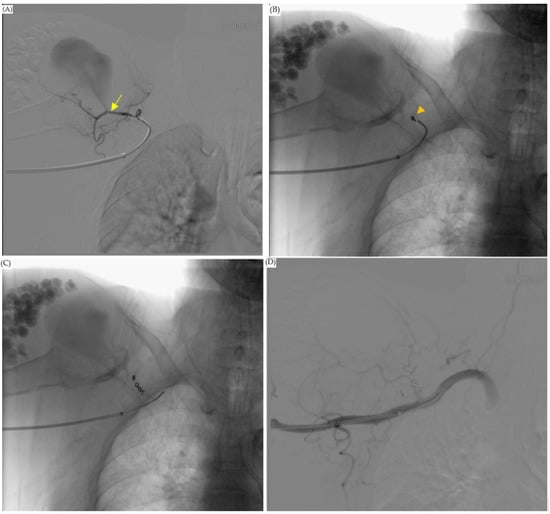

Figure 3.

Angiogram showed a pseudoaneurysm. (A) Angiogram showed that the feeding artery of the pseudoaneurysm was the thoracoacromial artery, acromial branch (arrow). Antibiotic beads were noted in this angiogram (arrowhead). (B) The aneurysm extended to acromion of scapula.

Figure 4.

Operation: embolization of the thoracoacromial artery, acromial branch. (A) Guidewire with JB1 catheter attached to the acromial branch. Contrast medium injected from JB1 catheter showed we entered our target. The aneurysm stump was also detected (arrow). (B) We used Tornado coils (arrowhead) to coil the feeding artery. (C) Three Tornado coils were inserted in the thoracoacromial artery, acromial branch. (D) At the end of the operation, angiogram showed total embolization of the feeding artery. There was no contrast pooling into the pseudoaneurysm.